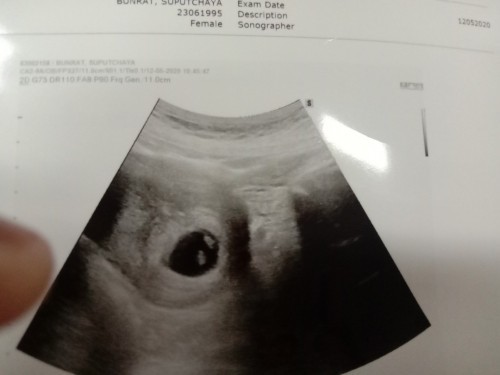

6สัปดาห์ค่ะ